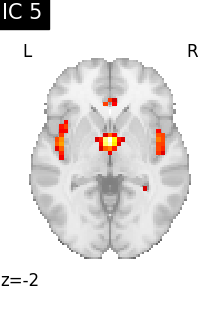

Finally, we plot the map for each ICA component separately

from nilearn.image import iter_img

from nilearn.plotting import plot_stat_map, show

for i, cur_img in enumerate(iter_img(canica_components_img)):

plot_stat_map(

cur_img,

display_mode="z",

title=f"IC {int(i)}",

cut_coords=1,

colorbar=False,

)